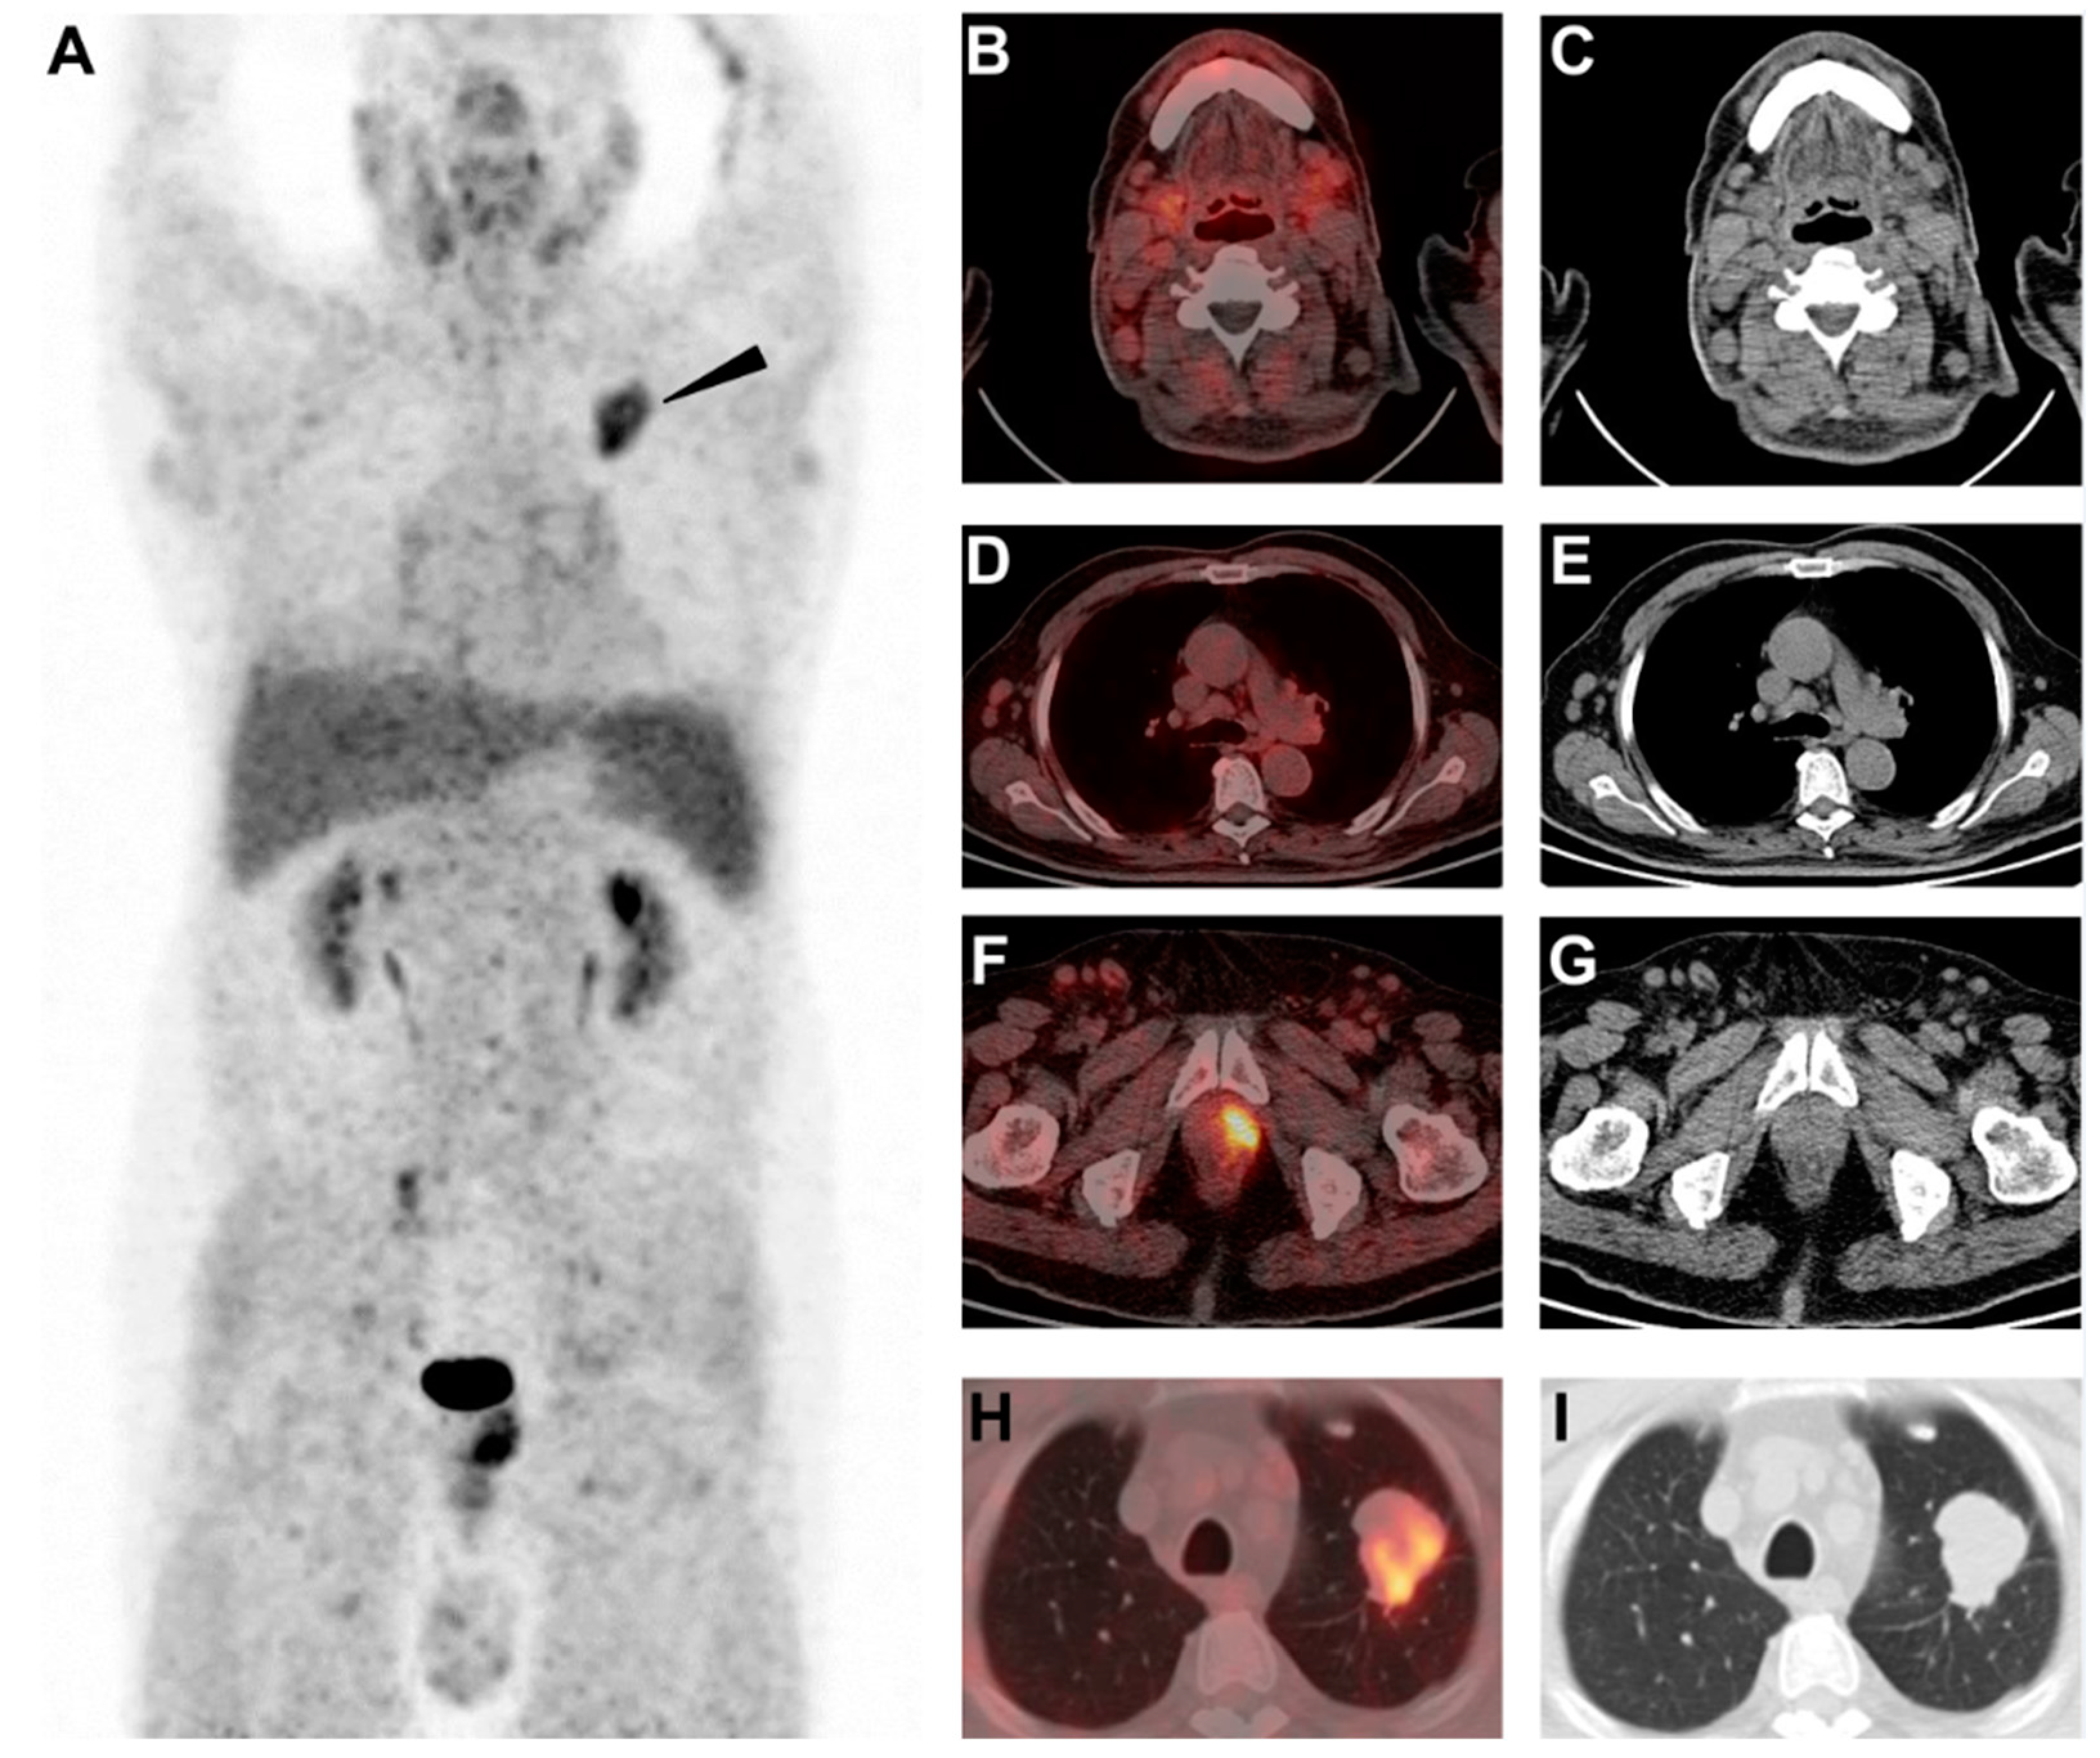

Different Uptake of 68Ga-FAPI and 18F-FDG in Lymphadenopathy Caused by Angioimmunoblastic T-Cell Lymphoma in a Patient with Colon Cancer

Wu, M.; Pan, Q.; Luo, Y. Different Uptake of 68Ga-FAPI and 18F-FDG in Lymphadenopathy Caused by Angioimmunoblastic T-Cell Lymphoma in a Patient with Colon Cancer. Diagnostics 2022, 12, 2211. https://doi.org/10.3390/diagnostics12092211